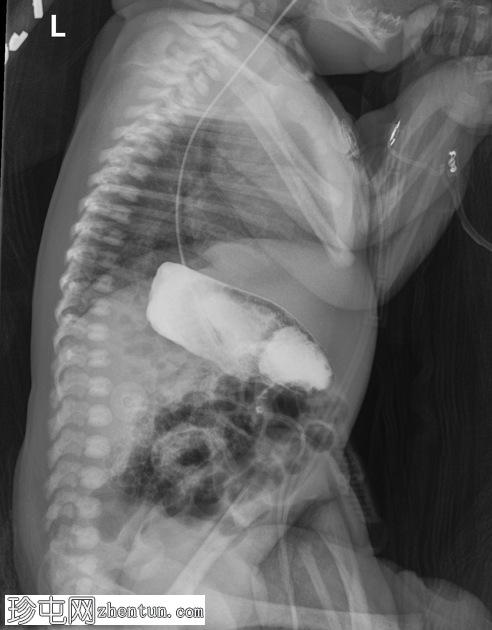

肺容量在正常范围内。可见轻度弥漫性颗粒状阴影。心脏大小和形态正常,心尖指向左侧。

腹部肠道气体分布无梗阻。经食管插管延伸至右侧腹部,提示胃位于右侧。左上腹密度增高,提示肝脏轮廓。